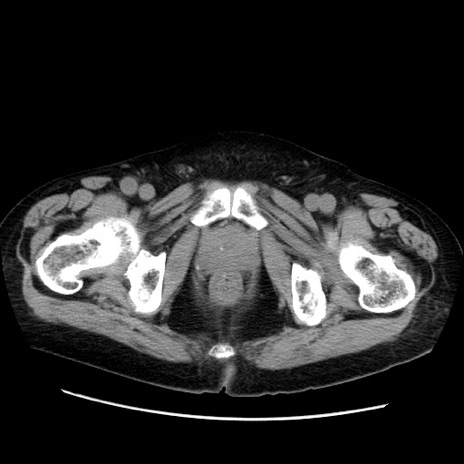

冠状断像